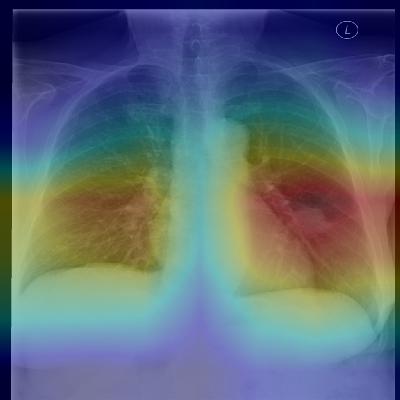

Figure 1: CheXNet is a 121-layer convolutional neural network that takes a chest X-ray image as input, and outputs the probability of a pathology. On this example, CheXnet correctly detects pneumonia and also localizes areas in the image most indicative of the pathology.

Our model, ChexNet (shown in Figure 1), is a 121-layer convolutional neural network that inputs a chest X-ray image and outputs the probability of pneumonia along with a heatmap localizing the areas of the image most indicative of pneumonia. We train CheXNet on the recently released ChestX-ray14 dataset (Wang et al., 2017), which contains 112,120 frontal-view chest X-ray images individually labeled with up to 14 different thoracic diseases, including pneumonia. We use dense connections (Huang et al., 2016) and batch normalization (Ioffe & Szegedy, 2015) to make the optimization of such a deep network tractable.